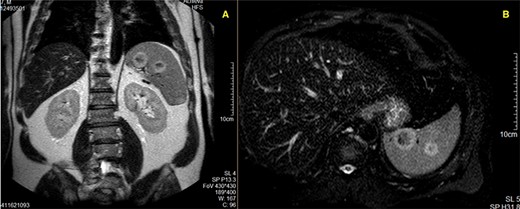

MR Imaging showing two nodular formations with the same ring-hypersignal pattern; A—T1-weighted acquisition; B—T2-weighted acquisition.

A magnetic resonance imaging (MRI) study (Fig. 2) was then ordered, and it described a spleen with regular margins and slightly enlarged, with its longitudinal axis measuring 14.3 cm. In the splenic parenchyma, multiple nodular lesions were detected, at least nine, with dimensions measuring up to 29 mm. These nodular formations were solid, heterogeneous, and showed a progressive and predominantly peripheral contrast-enhancement. They presented hyposignal in T1 and peripheral hypersignal in T2-weighted acquisitions, without any relevant restriction to diffusion. This absence of restriction to diffusion suggests benign nodularity; however, these features are not specific. Malignant splenic disorders could not be excluded.